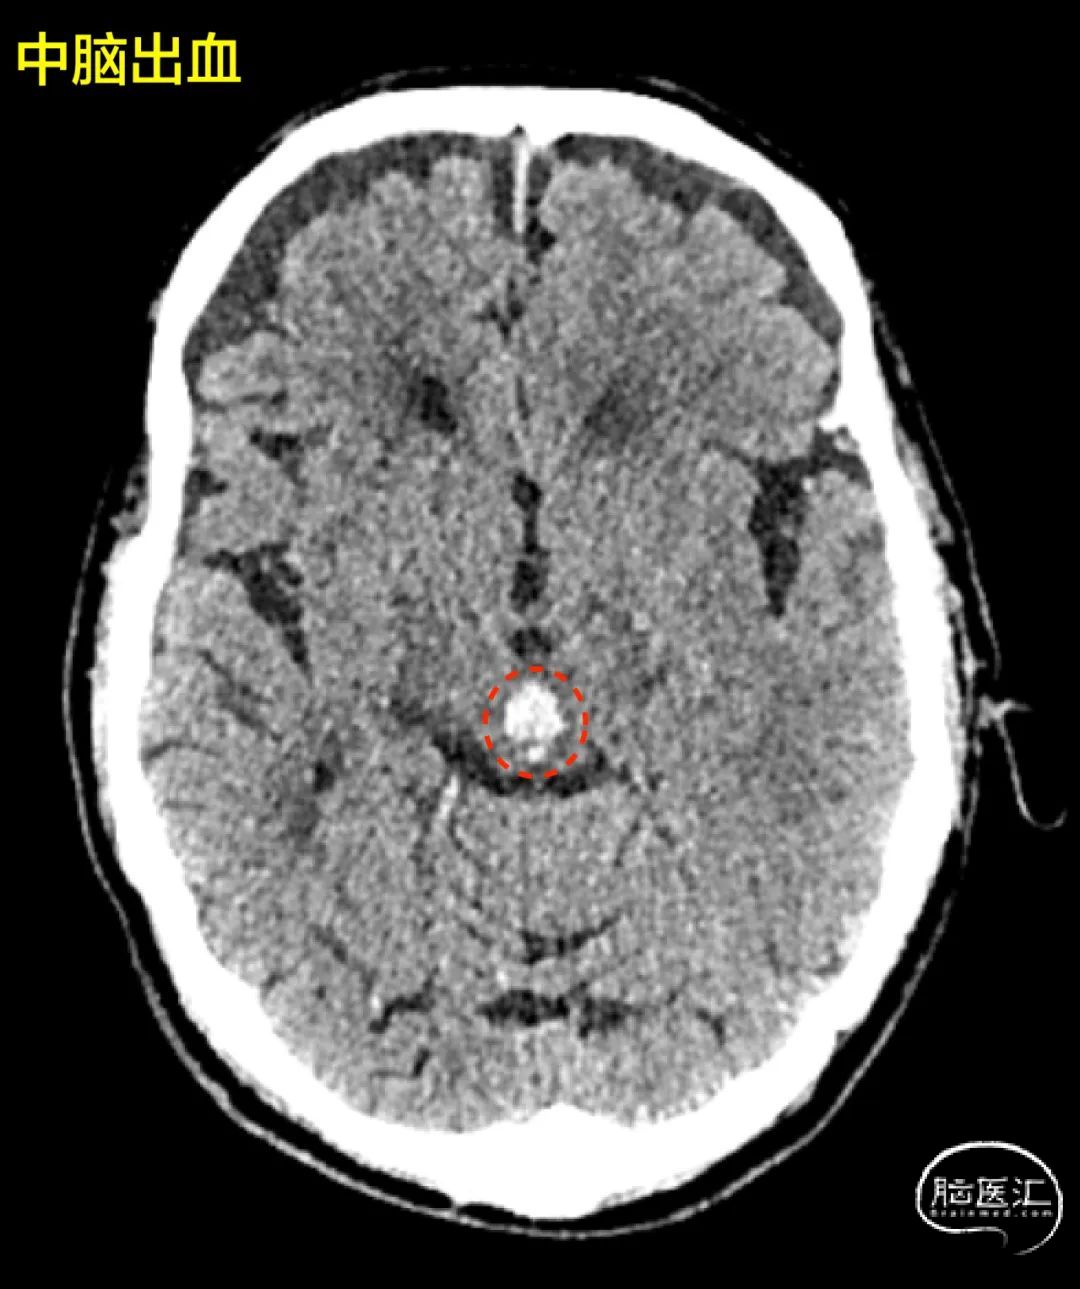

高血压性脑干出血、和海绵状血管瘤出血

一开始看片子不太容易分出来(主要看CT那些)

老年人啊,高血压闹起来,脑袋里出血就像炸弹爆炸,一般都是单个圆滚滚的球;

年轻力壮的中青年呢,要是摊上海绵状血管瘤,那形状就五花八门,歪歪扭扭的。